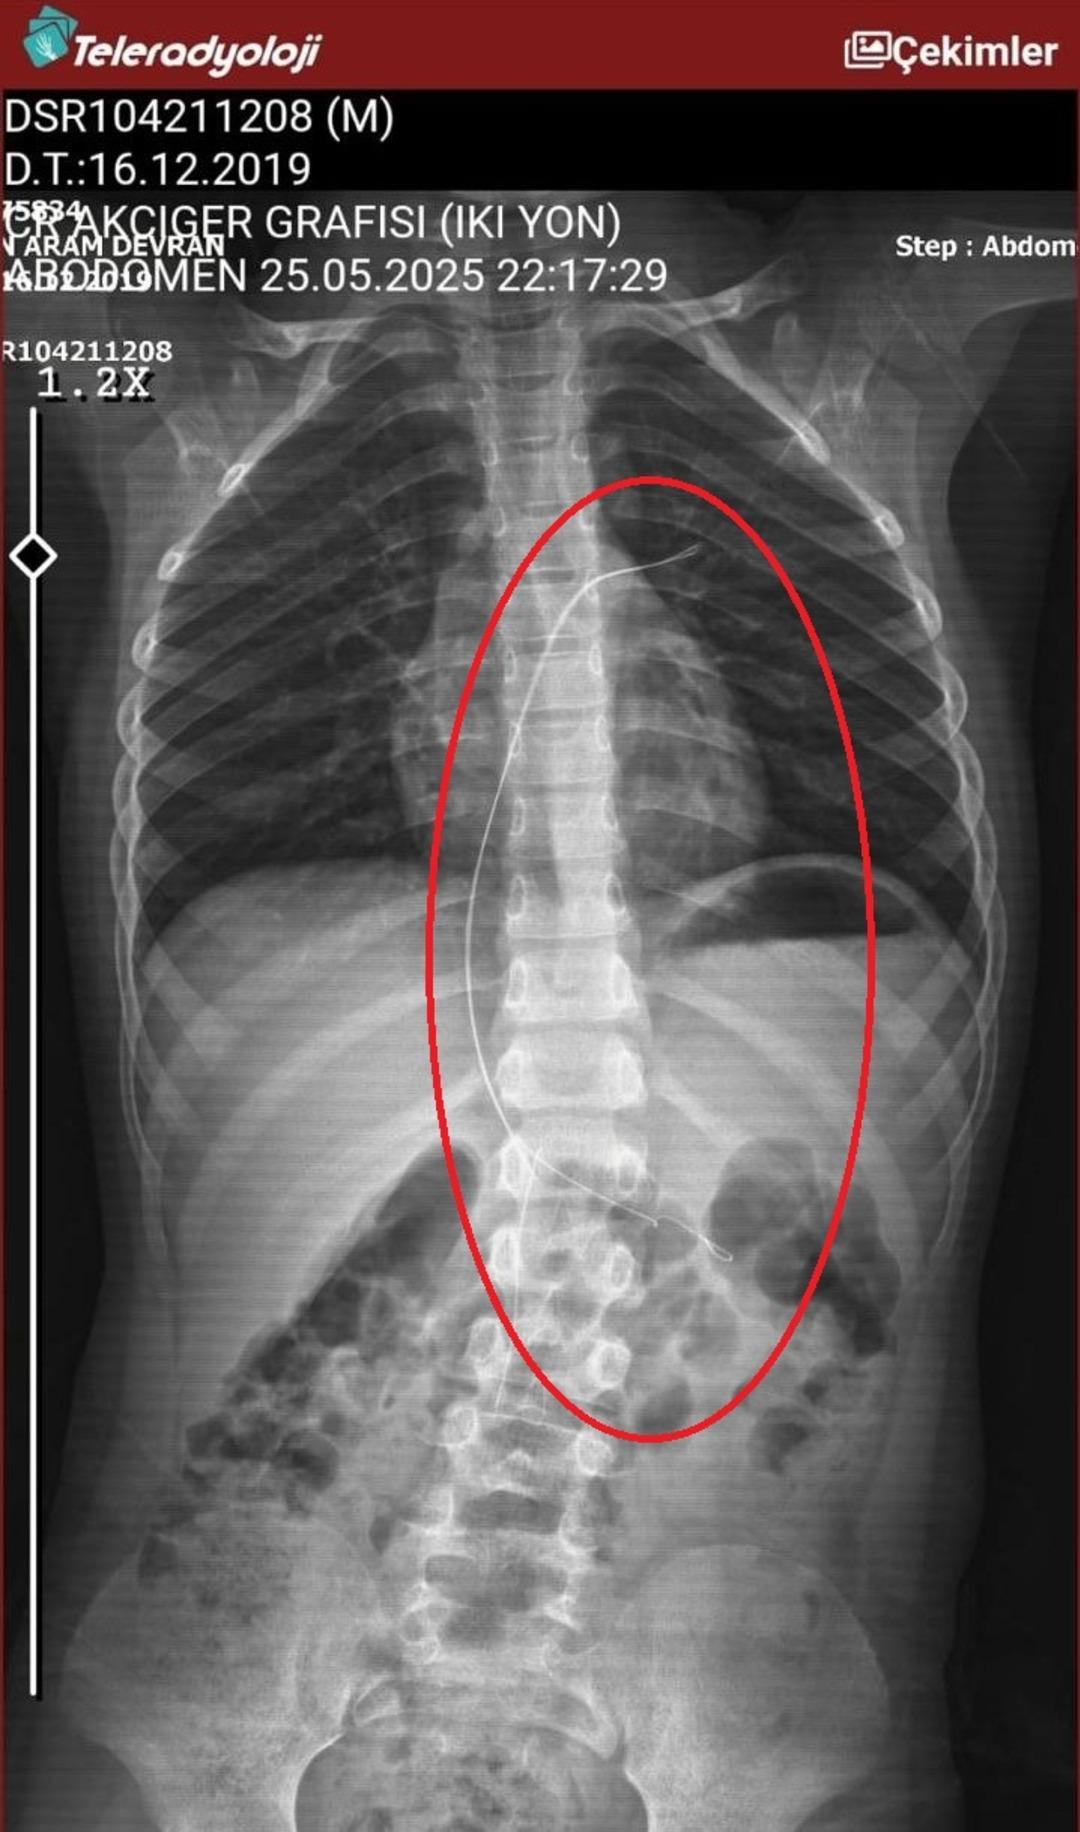

Seamore (37) ve Şaç'ta yaşayan Mehmet Ötün (40), Mayıs ayında bir parça salatalık yuttuktan sonra öksürük ve kusma şikayetleri gözlendiğinde Sernak Eyalet Hastanesine getirildi. Burada, ARAM gövdesinde yarıçap X ve manyetik rezonans görüntüleme unutuldu. Diyarbakir Gazi Yeşargil'in eğitim ve araştırma hastanesi jinekolojiye ve ARAM'lar için ek binaya yönlendirildi, 18 santimetrede 5.5 saatlik riskli cerrahi kaldırıldı. Postoperatif araştırmalarda, kateter kalp kapakına ve karaciğere zarar vermeye kararlıydı.